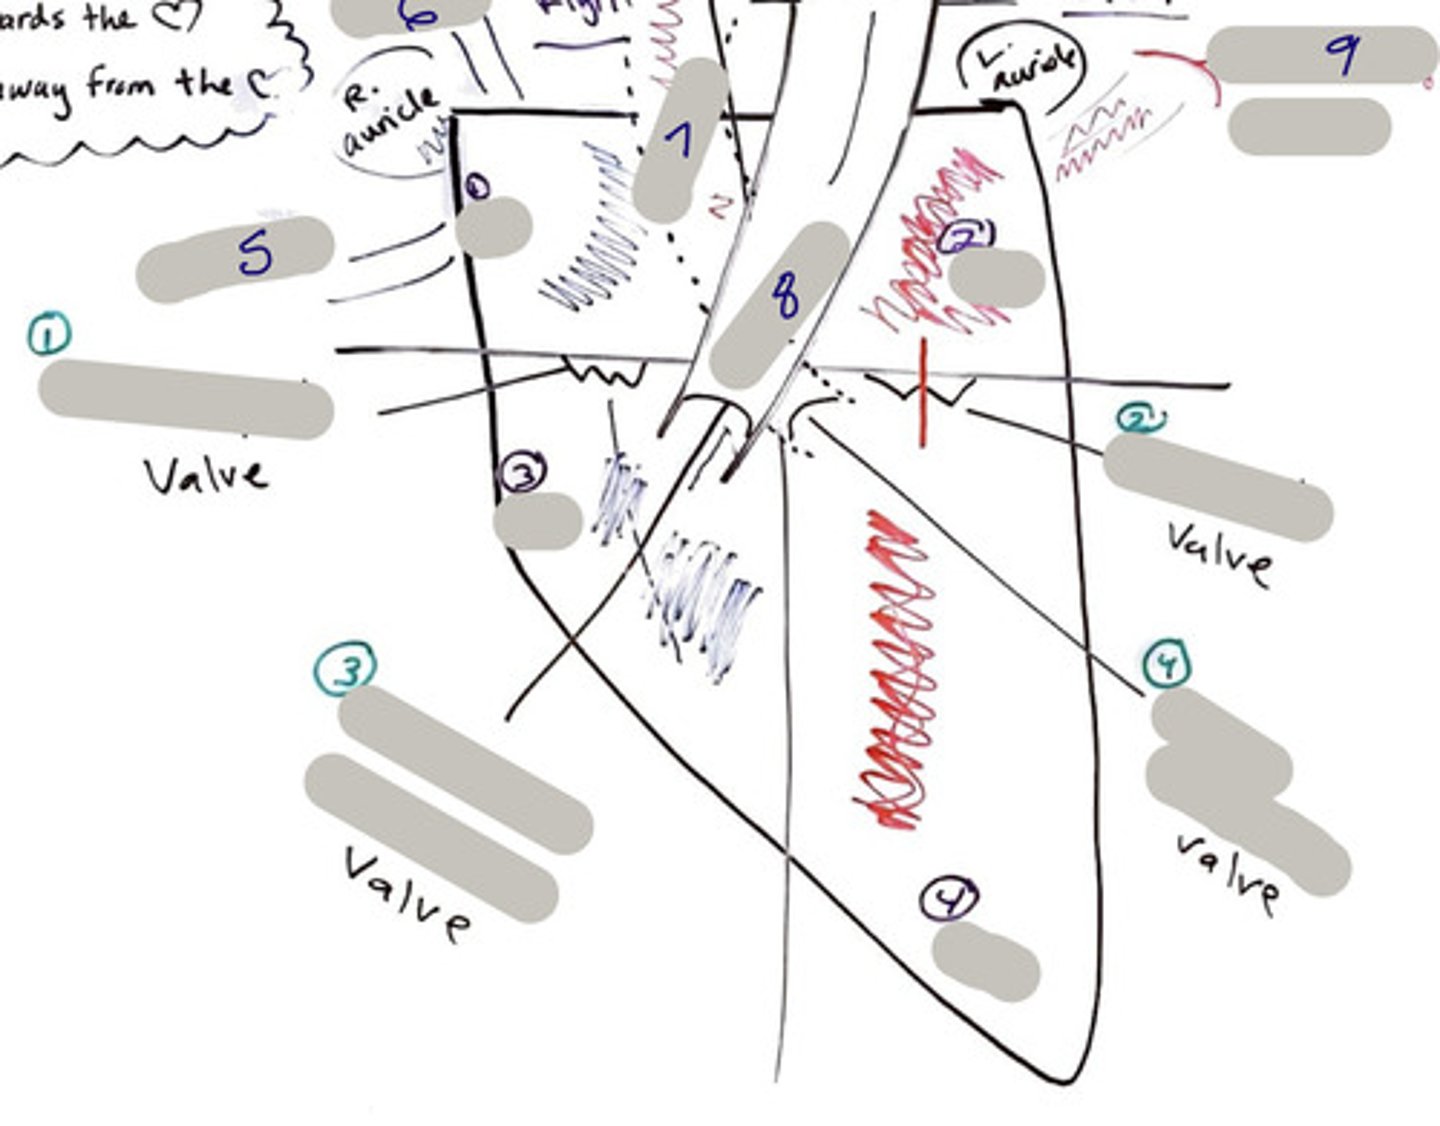

Tricuspid Valve (Right Atrioventricular Valve)

1-valve

Bicuspid valve (Left Atrioventricular Valve)

2-valve

Pulmonary Semilunar Valve

3-valve

Aortic Semilunar Valve

4-valve

Right Atrium

1-chamber

Left Atrium

2-chamber

Right Ventricle

3-chamber

Left Ventricle

4-chamber

Inferior Vena Cava

5-A vein that is the largest vein in the human body and returns blood to the right atrium of the heart from bodily parts below the diaphragm.

Superior Vena Cava

6-A vein that is the second largest vein in the human body and returns blood to the right atrium of the heart from the upper half of the body.

Aorta

7-The large arterial trunk that carries blood from the heart to be distributed by branch arteries through the body.

Pulmonary Trunk

8-carries blood from right ventricle to pulmonary arteries

Pulmonary veins

9-a vein carrying oxygenated blood from the lungs to the left atrium of the heart.